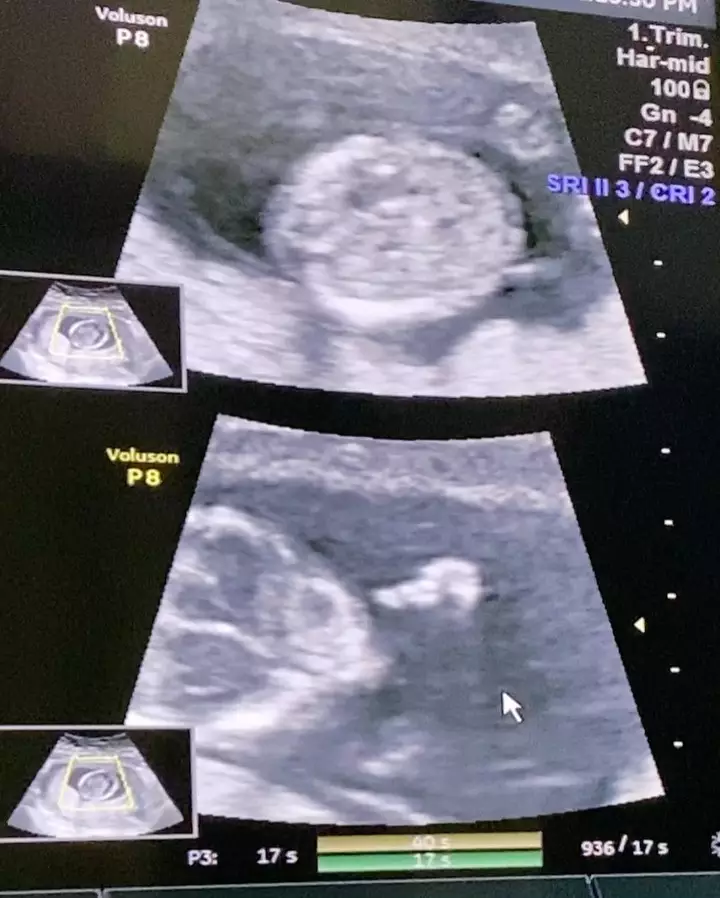

3. Sambil membawa foto USG yang menggambarkan janin mereka. Dion dan Fiona tak bisa menyembunyikan rasa bahagianya.

4. Dalam keterangannya, Dion menuliskan bahwa janinnya telah berusia 14 hari.

5. Di akhir slide fotonya, Dion juga mengunggah video saat janinnya bergerak.